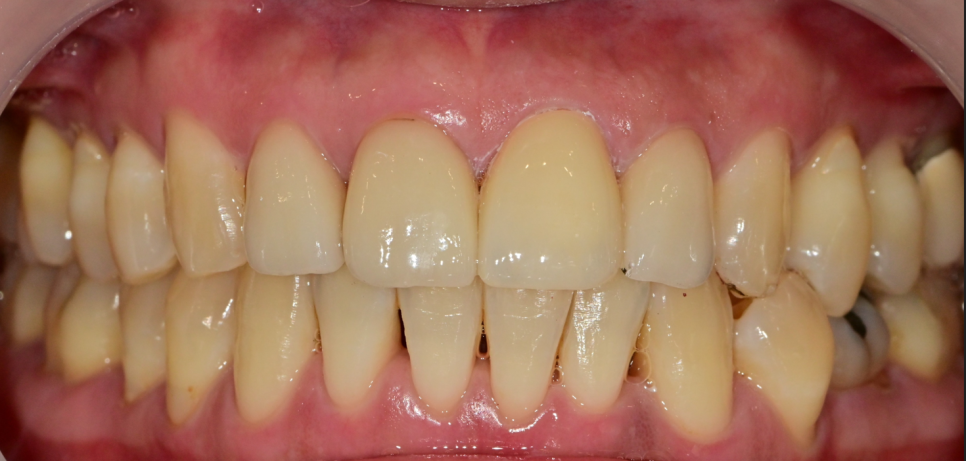

최종 보철물 부착 후의 사진입니다.

아직 남은 접착제를 완전히 제거하기 전에 찍은 것이라 조금 티가 납니다^^;

한 번에 만족스러운 결과가 나온 것 같아 당일 최종 부착을 해드렸습니다.

다행히 환자분도 만족하셨습니다.

주변 오래된 크라운들은 잇몸 쪽으로 조금씩 내려가 경계 부분이 조금씩 비춰 보이긴

하지만 크게 튀지 않는 상황이라 나중에 체크를 하며 지켜보기로 말씀드렸습니다.